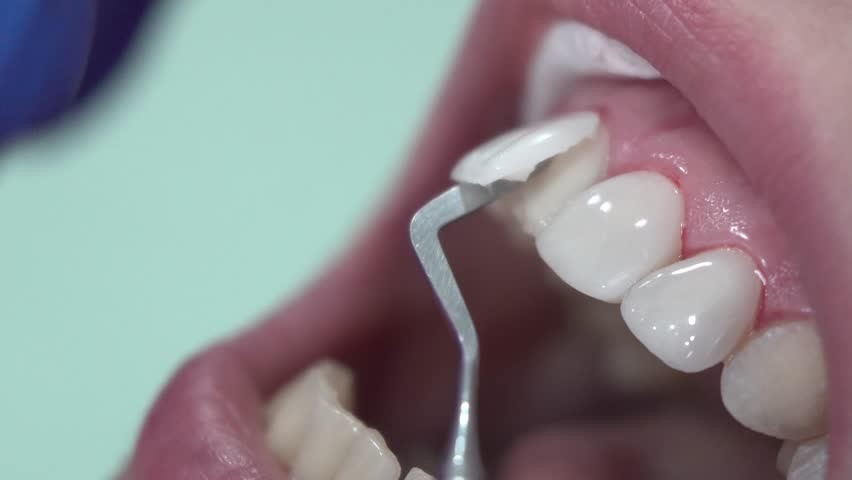

معمولاً کسانی که در معرض آسیب دیدگی مینای دندان قرار میگیرند باید به دندانپزشک ترمیمی و زیبایی مراجعه کنند که راهکارهای درمانی مختلفی برای آنها دارند. در اولین راهکار درمانی دندانپزشک از یک ماده به رنگ دندان که به آن رزین گفته میشود برای آغشته کردن و پوشش دادن سطح دندانها استفاده میکند و از این طریق قسمت آسیب دیده دندان را می پوشاند.

با توجه به اینکه امکان تغییر رنگ رزین وجود دارد و از دندان شما محافظت می کند، معمولاً اگر فرسایش مینای دندان منجر به تغییر رنگ دندان های جلویی شده باشد، متخصص این شیوه را پیشنهاد می کند.